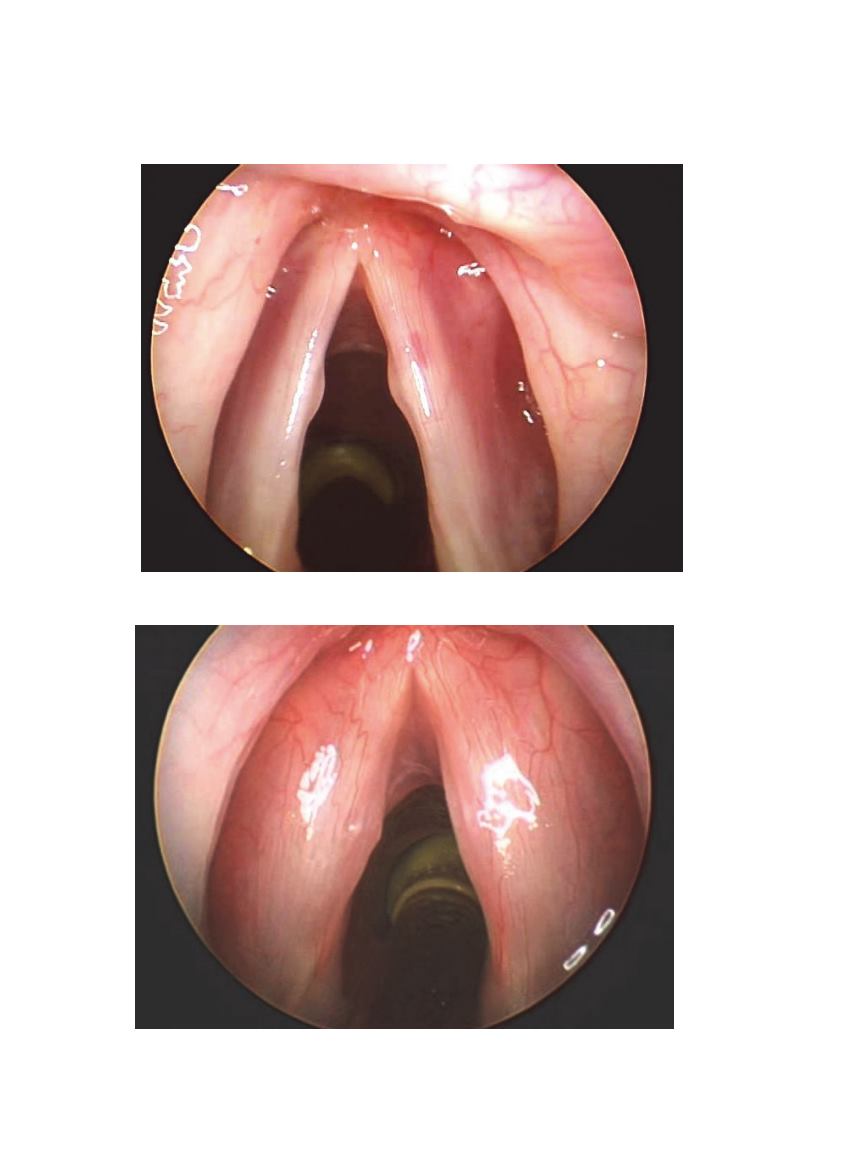

Nódulos vocales en estudiante de fonoaudiología, 22 años

Edema fusiforme y nódulos vocales mujer 17 años